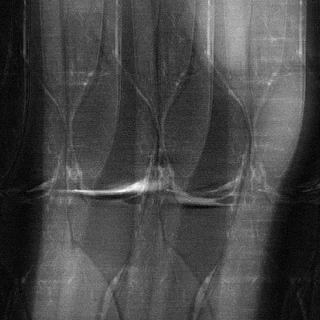

ニューヨーク大学医学部放射線科教授のダニエル・ソディクソン氏によると、MRIスキャンが遅い理由は、放射線科医が読影しやすい鮮明な画像を生成するために必要なデータをすべて取得する必要があるためです。膝のスキャンには15~20分、脳のスキャンには30分、心臓の撮影には1時間かかります。しかし、もしMRI装置の動作速度を上げて、なおかつ実用的な画像を取得できたらどうなるでしょうか?

このプロジェクトは、医療に人工知能を取り入れる興味深いアプローチを示しています。AIは画像に写っているものを分析するために頻繁に利用されています。日常生活においては、例えばYelpにアップロードされたパスタやホットドッグの写真などがその例です。また、X線写真などの医療画像の場合、X線写真中の結核やMRIで撮影された膝の画像をAIで分析する研究が行われています。さらに、Alphabet傘下のDeepMindと英国のMoorfields Eye Hospitalの共同研究では、AIが患者の眼底の3次元スキャン画像を分析し、治療法の提案まで行う予定です。

もちろん、通常よりも少ないデータから画像を作成するのはリスクがあるように聞こえます。AIがデータを解釈して見栄えの良い画像を生成したとしても、何か重大なものを見逃していたらどうなるでしょうか?靭帯の小さな裂傷や小さな腫瘍など?ソディクソン氏によると、それが彼らの最大の懸念事項だそうです。「提示している情報が真実であることを確認する必要があります」と彼は言います。「それを検証する方法はたくさんあります。」